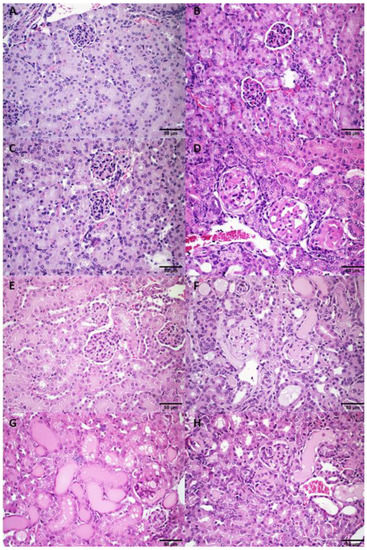

3.3.2. Histological Analysis